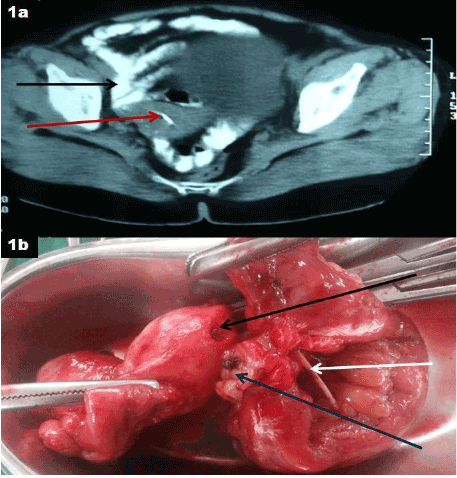

图1a:CECT骨盆显示肠环附着于子宫底(黑色箭头),造影剂外渗至宫腔(红色箭头),提示有肠-子宫瘘。

图1b:切除标本显示宫内节育器(白色箭头)和子宫底(黑色箭头)与小肠袢(蓝色箭头)之间的瘘管连通。

一位59岁绝经后女性患者,表现为持续性阴道分泌物和持续2年的隐匿下腹疼痛。无发热或肠道或膀胱紊乱史。她过去曾多次接受抗生素治疗,但没有明显缓解。阴道检查显示子宫压痛她是5个孩子的母亲,最后一次分娩是在25年前。由于对骨盆的超声检查不确定,对比增强计算机断层扫描(CECT)对骨盆进行检查,发现一个小肠环附着在子宫底,口腔造影剂漏入子宫,提示有肠子宫瘘(图1a).剖腹探查时,回肠袢紧密附着于子宫底。进行子宫切除术,切除受累的小肠袢,然后进行端到端的手工缝合肠吻合。对切除标本的检查显示IUCD是瘘管的原因(图1b)术后过程平安无事,患者回忆起上次分娩后放置了宫内节育器,从未取出。